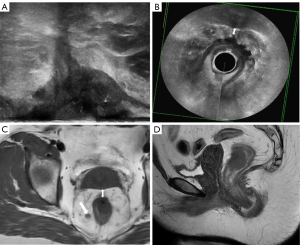

The T-staging was evaluated according to the eighth edition of the TNM classification system (15). According to the guidelines of European Society for Medical Oncology (ESMO) published in 2017 (16), MRF invasion on MRI and 3D-ERUS was compared with pathology measurements using a 1-mm criterion (Figure 1).